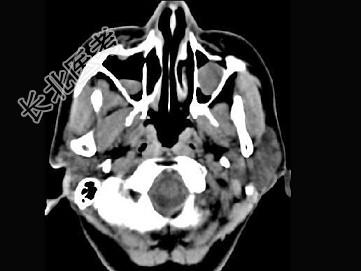

- 单项选择题男,7岁, 无明显症状,CT如图所示, 最可能的诊断是 ( )

A、上颌窦淋巴瘤

B、上颌窦炎

C、上颌窦黏膜下囊肿

D、上颌窦乳头状瘤

E、鼻炎及副鼻窦黏膜下囊肿